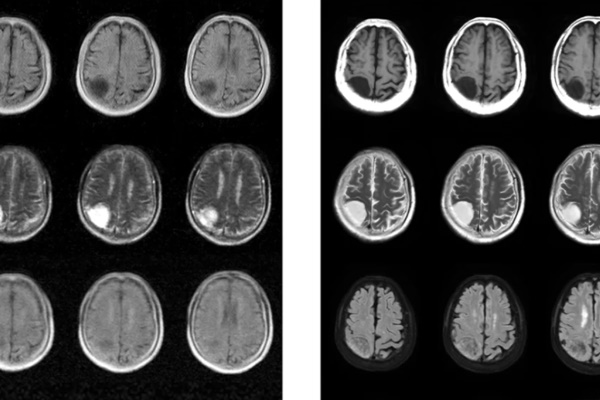

수억원대 장비를 수천만원대로···자기장까지 줄인 이동식 MRI 등장

비용을 획기적으로 줄이고 훨씬 낮은 전력과 자기장을 사용해 뇌질환을 감지하는 이동식 자기공명영상법(MRI) 장치가 홍콩대 연구진에 의해 개발됐다. MRI는 강력한 진단...